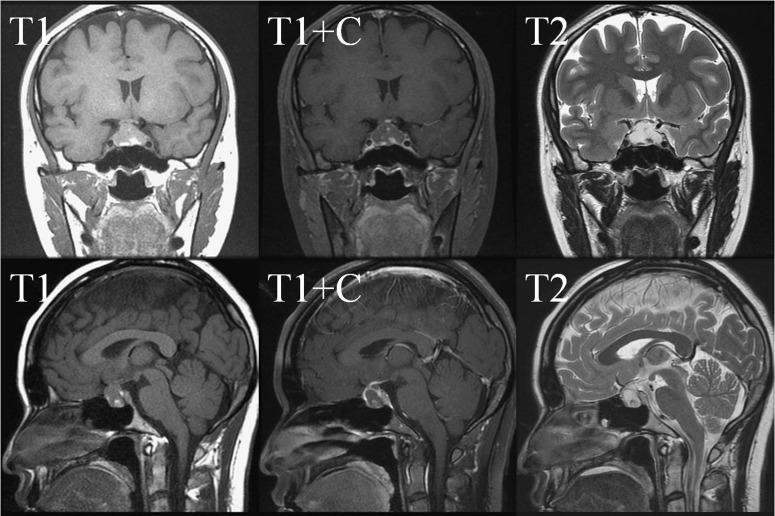

Pituitary spindle cell oncocytoma presented as pituitary apoplexy.

Spindle cell oncocytoma is a rare nonfunctioning neoplasm of the adenohypophysis, and was first described in 2002 by Roncaroli In 2007, spindle cell oncocytoma has been categorized as a separate entity by the World Health Organization (WHO) and is classified as a Grade 1 tumor of the central nervous system. Spindle cell oncocytoma of pituitary gland usually occurs in adults and accounts for 0.1-0.4% of all sellar region tumors. Clinically and radiologically, they are indistinguishable from nonfunctioning pituitary adenomas. From 2002 to 2018, approximately 46 cases of spindle cell oncocytoma of pituitary gland had been reported in the English literature and we would like to report a case of 28-year-old woman presented with pituitary apoplexy proved to be a case of spindle cell oncocytoma of pituitary gland which probably will be the 47th reported case.